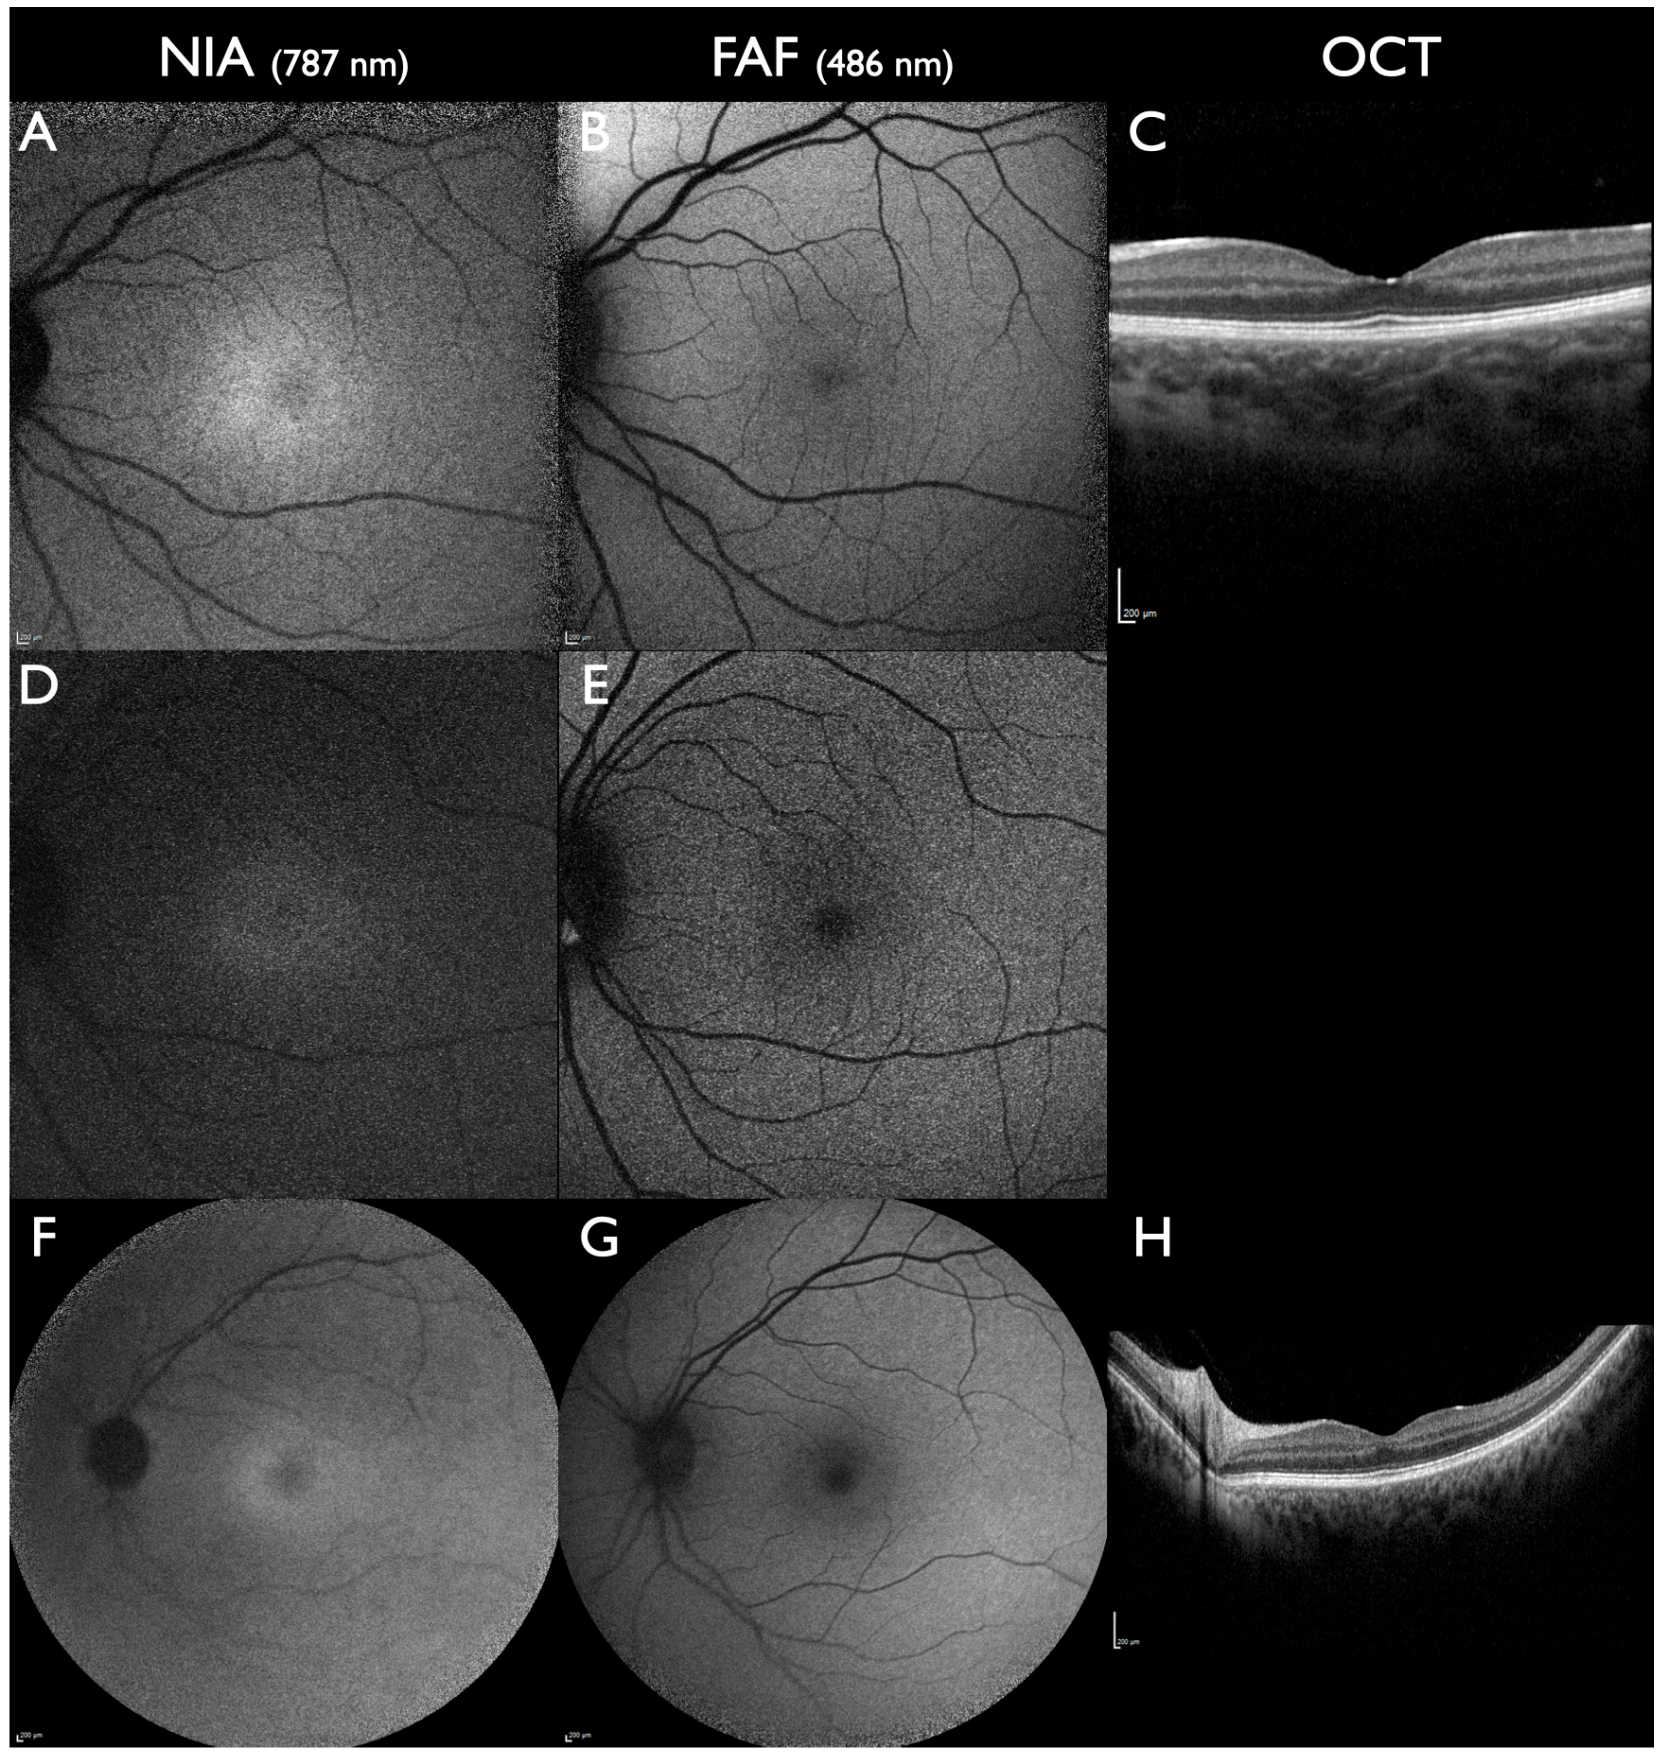

Best disease is known for incomplete penetrance. The earliest biomarker in a preclinical stage of Best disease is a subfoveal reduced NIA intensity [29]. In this stage, FAF, OCT, and ophthalmoscopy are completely normal (Figure 3). In non-manifesting carriers of Best disease, a subfoveal reduced NIA intensity remains the only detectable biomarker (Figure 3). In the next step, while ophthalmoscopy is still normal, initial alterations of the outer retinal layer in OCT and the foveal avascular zone in the deep retinal plexus in OCTA can develop [63].

Figure 3. BEST1-associated macular dystrophy in subclinical stages. All patients had one pathogenic gene sequence variant in the BEST1 gene (AC): A 3-year-old female. Visual acuity 20/20; visual fields not tested due to age. Reduced subfoveal NIA intensity and normal FAF and OCT. (D,E): A 40-year-old female, aunt of the previous patient. Visual acuity 20/20; visual fields normal. Reduced subfoveal NIA intensity and normal FAF; OCT not performed. (FH): A 44-year-old female from a different family. Visual acuity 20/20; visual fields normal. Reduced subfoveal NIA intensity and slightly increased parafoveal FAF intensity; normal OCT. All scale bars indicate 200 µm.